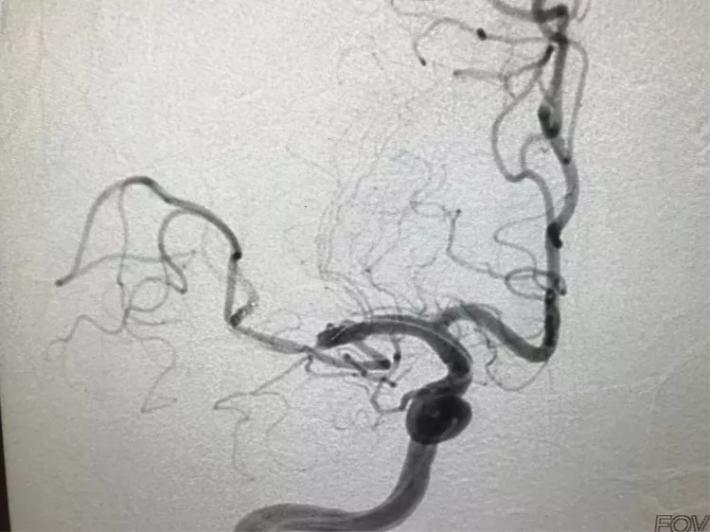

脑血管造影显示:右侧大脑中动脉闭塞。

手术步骤

微导管进入大脑中动脉远端真腔。

置入支架,见大脑中动脉有血流。

取出支架,血管未开通。

再次上微导管。

微导管进入大脑中动脉远端真腔。

第二次置入支架取栓。

血管仍未开通。

第三次上微导管。

再次置入支架取栓。

见血管再通。